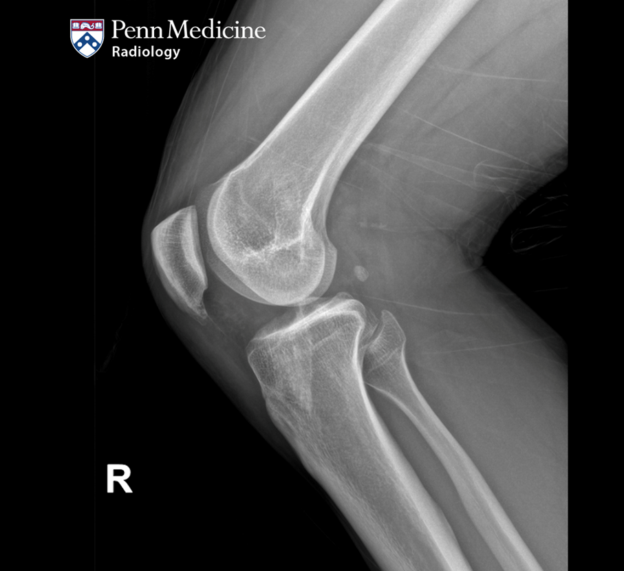

33-year-old man with right knee pain and swelling

A 33-year-old man presented to the orthopedics clinic with right knee pain and swelling.